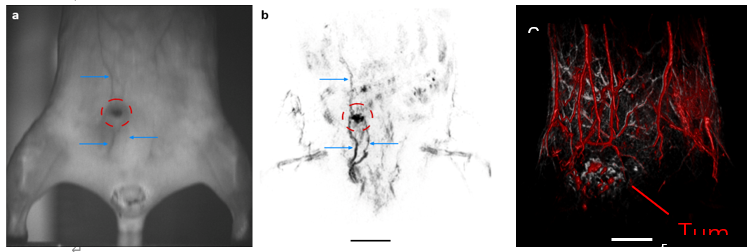

無毛小鼠(左)和 nu/nu 小鼠(右)中的人類乳腺癌異種移植(BT474 細(xì)胞)。(a、b)顯示了相機(jī)觀察結(jié)果和相應(yīng)的冠狀 MIP 板,由 700 nm 和 1064 nm 激光激發(fā)獲得的 TriTom 圖像構(gòu)建而成。藍(lán)色箭頭和紅色 ROI 表示高分辨率圖像中可見的淺表血管特征和腫瘤環(huán)境。(c)復(fù)合皮膚(532 nm;灰色)和深層組織(890 nm;紅色)3D 圖像。腫瘤大小 = 10.6 x 4.7 x 11.6 mm3